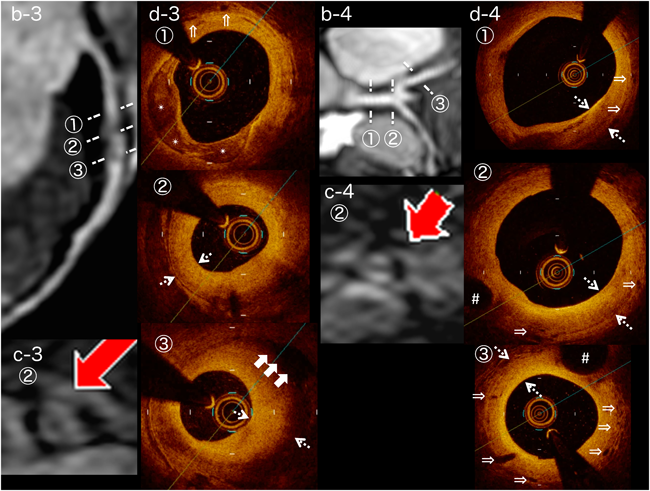

Fig. 3 Image findings for Cases 3 and 4

(Case 3) Localized stenosis is seen at segment 6. In vessel wall imaging, thickening is seen at the lesion (b-3, c-3). On the optical coherence tomography (OCT) image (d-3), intimal hyperplasia with fibrosis (arrows), calcification (asterisks), neovascularization (double arrows), and separation of the media (white arrows) are apparent. (Case 4) The aneurysm at the bifurcation of the left coronary artery has regressed. Upon vessel wall imaging, thickening is apparent at the lesion. This lesion shows intimal hyperplasia with fibrosis (d-4, arrows) and neovascularization (double arrows) on OCT. Side branches originate from the coronary artery (hash marks).